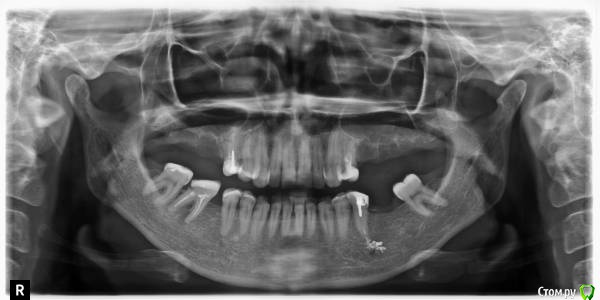

S-Sity Опубликовано 24 декабря, 2014 Поделиться Опубликовано 24 декабря, 2014 Добрый день! Подскажите что делать с зубом, у которого при лечении вывели пломбировочный материал?http://www.photohost.../400/752814.jpg Ссылка на комментарий

S-Sity Опубликовано 24 декабря, 2014 Автор Поделиться Опубликовано 24 декабря, 2014 До вчерашнего дня ничего не беспокоило. Но вчера почувствовала боль.Больно нажимать на десну под зубом.Зуб придется убрать? Ссылка на комментарий